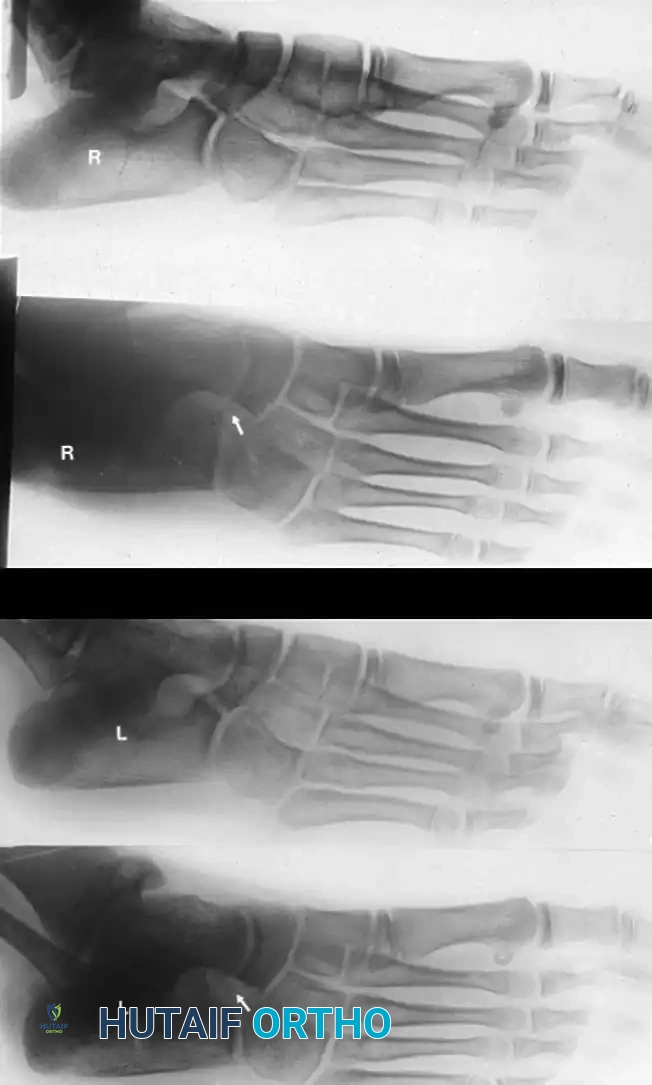

- الأشعة السينية (X-rays):

- للتشخيص المبدئي، يتم التقاط صور بوضعيات خاصة.

- لتشخيص التحام العقب والزورقي، تعتبر الصورة المائلة بزاوية 45 درجة هي الأفضل.

- لتشخيص التحام الكاحل والعقب، يتم استخدام وضعية خاصة تسمى (Harris-Beath view) لتصوير المفصل الأوسط.

- الأشعة المقطعية (CT Scan): تعتبر المعيار الذهبي لتشخيص التحام الكاحل والعقب. توفر صوراً ثلاثية الأبعاد ومقاطع عرضية دقيقة توضح حجم الالتحام، موقعه، وحالة المفاصل المجاورة، مما يساعد الجراح في التخطيط للعملية.